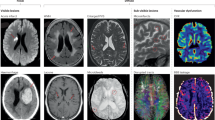

Small vessel disease (SVD) refers to a group of pathological processes with various aetiologies involving perforating cerebral arterioles, venules and capillaries, resulting in damage of cerebral white and deep grey matter. It includes lacunas, recent small subcortical infarcts, white-matter hyperintensities (WMH), perivascular spaces (PVS), micro bleeds (MB) and brain atrophy1. Several Authors refer to the most common form as the so-called “age-related SVD”, that is considered to be related to physiological ageing and classical vascular risk factors2.

The inclusion criteria for patients were: (i) age between 18 and 65 years; (ii) white matter hyperintensities on T2-weighted/fluid attenuation inversion recovery (FLAIR) sequences at brain MRI performed with high field equipment (1,5 T), defined using STRIVE consensus1 and categorized by Fazekas score32. An expert neurologist who evaluated axial-FLAIR imagines of brain MRI calculated WMH scoring.